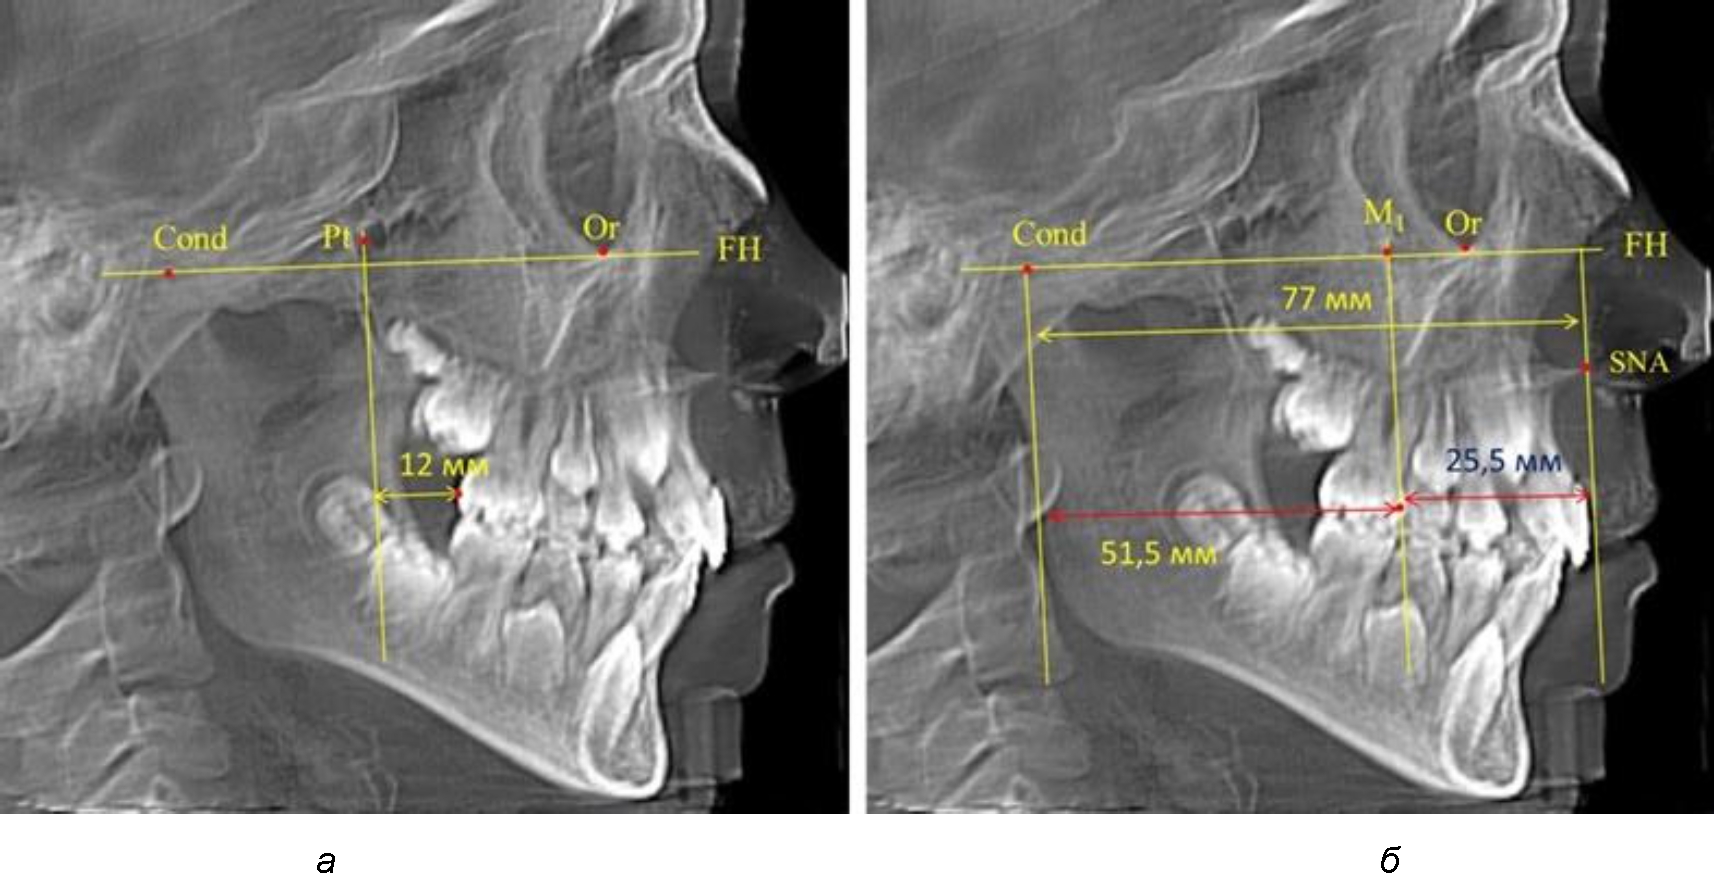

По мере роста челюстей увеличивалась глубина гнатического отдела лица, и кондиллярно-спинальный размер составлял в среднем (74,57 ± 0,93) мм. Дистальная поверхность первого постоянного моляра отстояла от крыловидной вертикали на величину, составляющую около 11 мм, что, так же, как и в периоде прикуса молочных зубов, было близким по значению к данным R. E. McDonald, а именно возраст, плюс 3 мм. Однако величина ошибки среднего значения свидетельствовала о вариабельности признака даже в восьмилетнем возрасте после замены передней группы зубов и установки ключевых постоянных моляров в окклюзионное равновесие. Обращает на себя внимание отношение глубины гнатического отдела лица к дистальному отделу, а именно к кондилярно-молярному расстоянию (рис. 5).

Рис. 5. Особенности положения первых моляров по R. E. McDonald (а) и по предложенному методу (б) у ребенка 8 лет

После прорезывания вторых постоянных моляров кондилярно-спинальный увеличивался до 80 мм.

Дистальная поверхность первого постоянного моляра отстояла от крыловидной вертикали на величину, составляющую около 18 мм, что, так же, как и в предыдущих периодах прикуса, было близким по значению к данным R. E. McDonald, а именно возраст, плюс 3 мм.

Обращает на себя внимание отношение глубины гнатического отдела лица к дистальному отделу, а именно к кондилярно-молярному расстоянию, которое, вне зависимости от сагиттальных размеров, составляло 1 : 1,5.